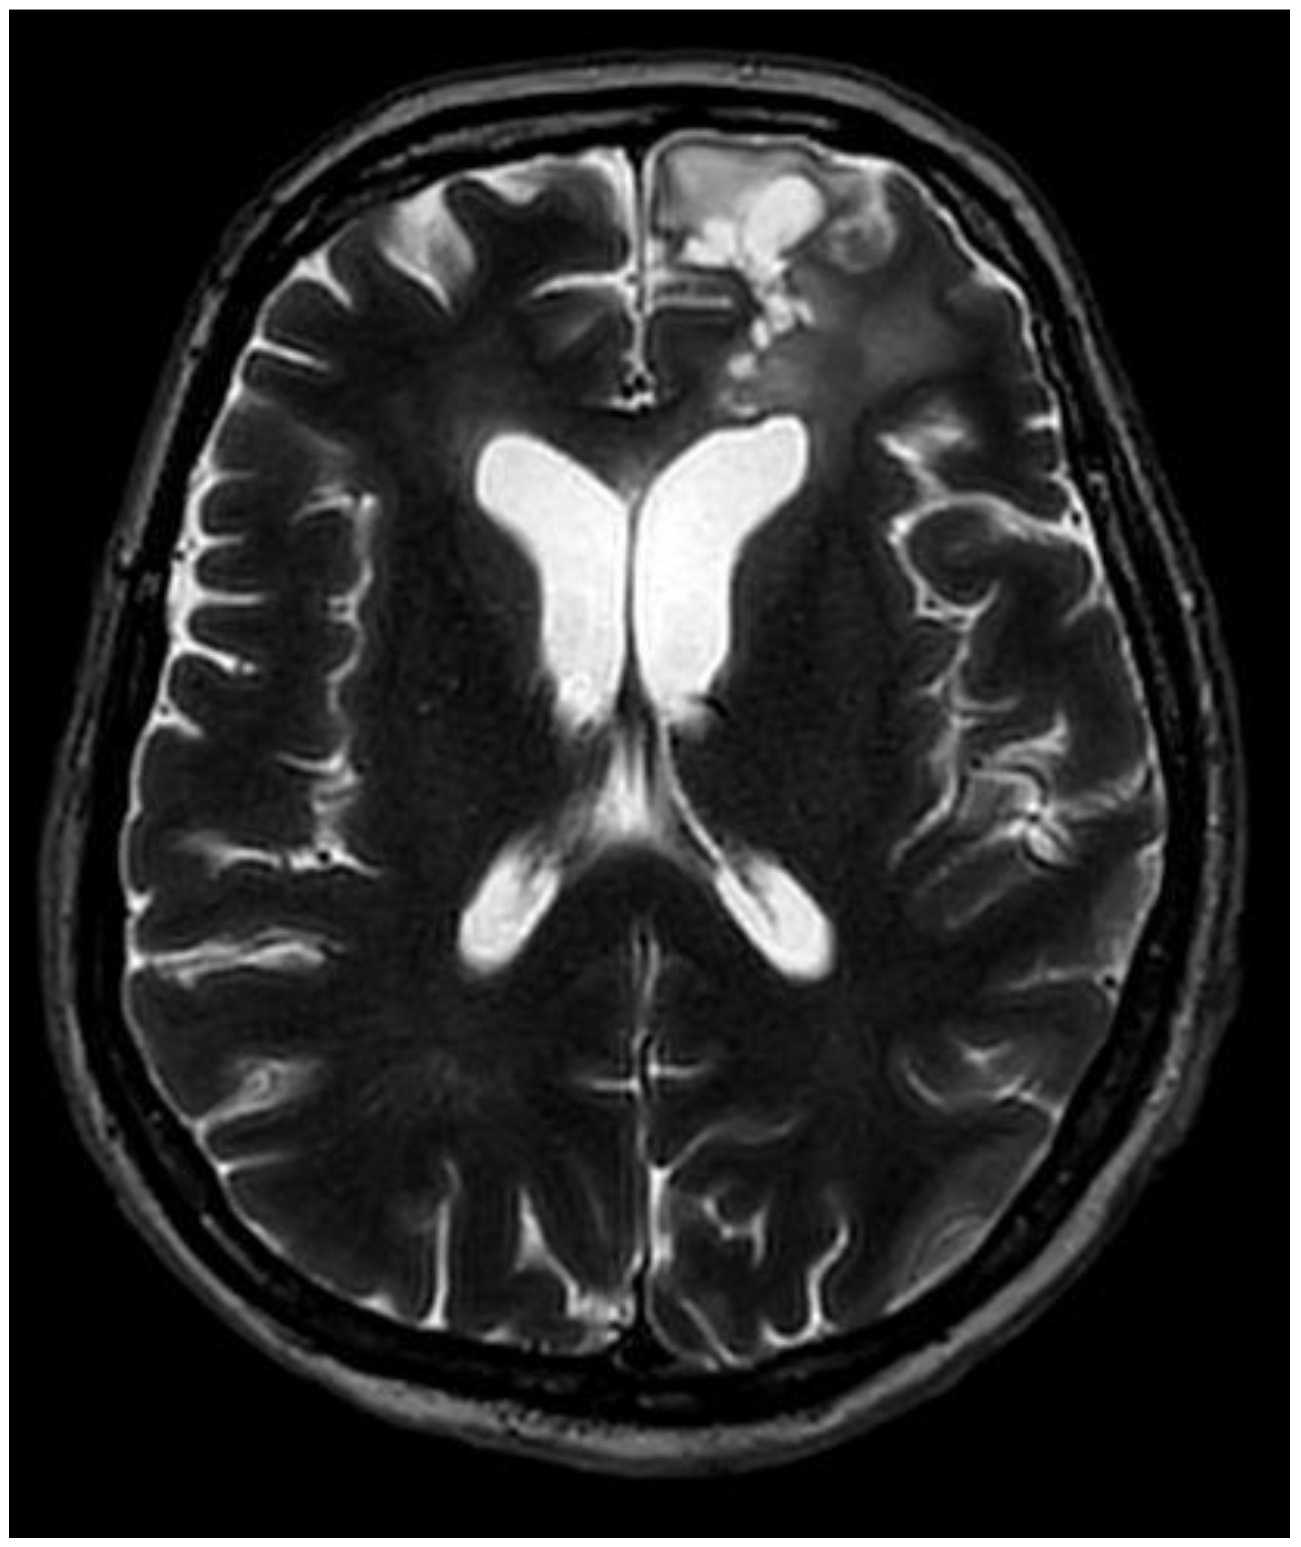

2. Case Presentation